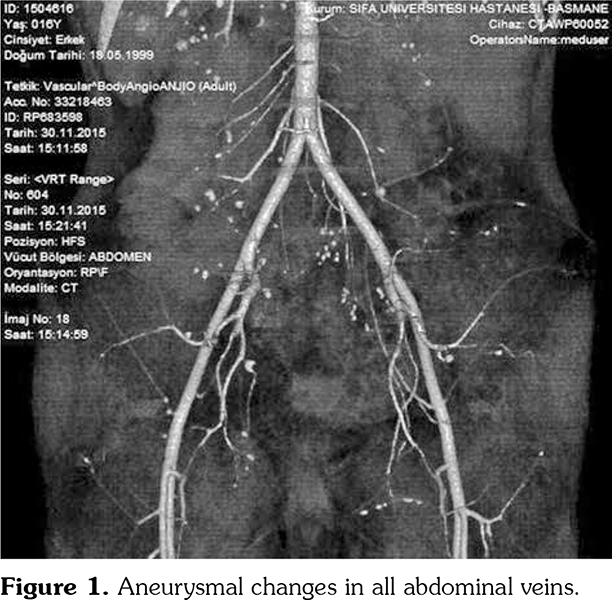

A 17-year-old male patient presented to the emergency department for evaluation of severe abdominal pain of approximately two months duration. His past history revealed that an abdominopelvic ultrasonography and a computed tomography angiography were performed before he was referred. They showed aneurysmal changes in all abdominal veins (Figure 1). Physical examination was notable for a blood pressure of 200/100 mmHg, paleness, myalgia in the legs and arms, and abdominal sensitivity. His weight and height were 28 kg (-3.7 standard deviation [SD]) and 149 cm (-3.89 SD), respectively. Laboratory evaluation revealed anemia (hemoglobin 9.6 g/dL, mean corpuscular volume: 64.3 fL) and elevated acute phase reactants (erythrocyte sedimentation rate: 82 mm/hour, C-reactive protein: 205.2 mg/dL). Urinary analysis showed +3 proteinuria. Complement components (C3, C4), antistreptolysin O, viral serologies, perinuclear antineutrophil cytoplasmic antibodies, and antineutrophil cytoplasmic antibody were observed as negative. The patient was accepted as PAN due to the imaging results, weight loss, myalgia, and renal involvement. For blood pressure elevation; sodium nitroprusside infusion was applied at first and then calcium channel blocker and angiotensin-converting-enzyme inhibitor were administered. During follow-up, he had a suspect seizure attack and complained of temporary loss of vision. A written informed consent was obtained from the patient.

Cranial magnetic resonance imaging (MRI) and diffusion imaging were normal. Regarding the diagnosis of PAN, administration of pulse methylprednisolone (PMP) was planned at a dose of 30 mg/kg and 500 mg/m2/day intravenous (IV) cyclophosphamide treatment. Due to insufficient oral intake and continuous stomach pain, total parenteral nutrition was started. Additional PMP treatments were added for the case from whom partial clinical and laboratory response were obtained in the follow-up. After nine doses of PMP and two IV cyclophosphamide treatments, administration of infliximab, a tumor necrosis factor-alpha (TNF-α) blocker, was planned. In the first month of follow-up, the patient, who had aggravated stomach pain, was assessed as intestinal perforation. Total ileum and column resection were applied and jejunostomy was performed (Figure 2). Pathological examination indicated fibrinoid necrosis in small and middle veins that was compatible with PAN (Figure 3). The patient was taken to intensive care unit with postoperative sepsis and a new perforation that was observed in the second exploration. He was exitus on the 44th follow-up day. Genetic studies showed V726A heterozygous mutation in Mediterranean fever (MEFV) gene and p.G47A (c.140 G>C homozygous mutation in CECR1 gene).